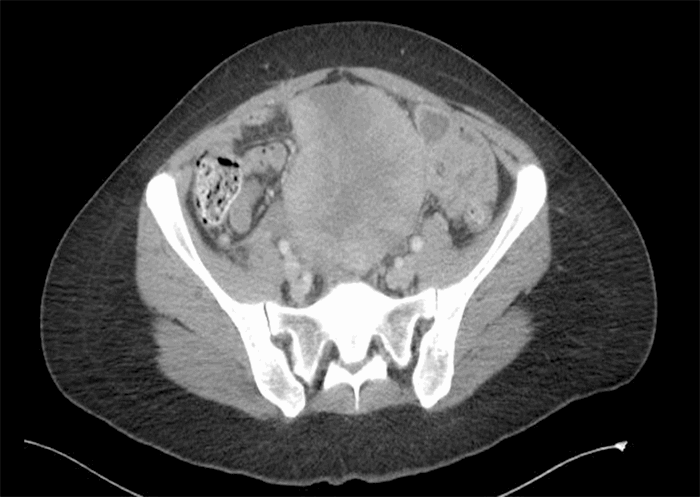

The patient is a 35-year-old female with no significant past medical history who presented with acute onset of abdominal pain and distension. A CT abdomen/pelvis showed a large heterogeneous partially necrotic lower mid-intraabdominal mass and a small volume of ascites (Figure 1 and Figure 2).

Figure 2. CT abdominal/pelvis axial section re-demonstrates large lower-mid intraabdominal mass